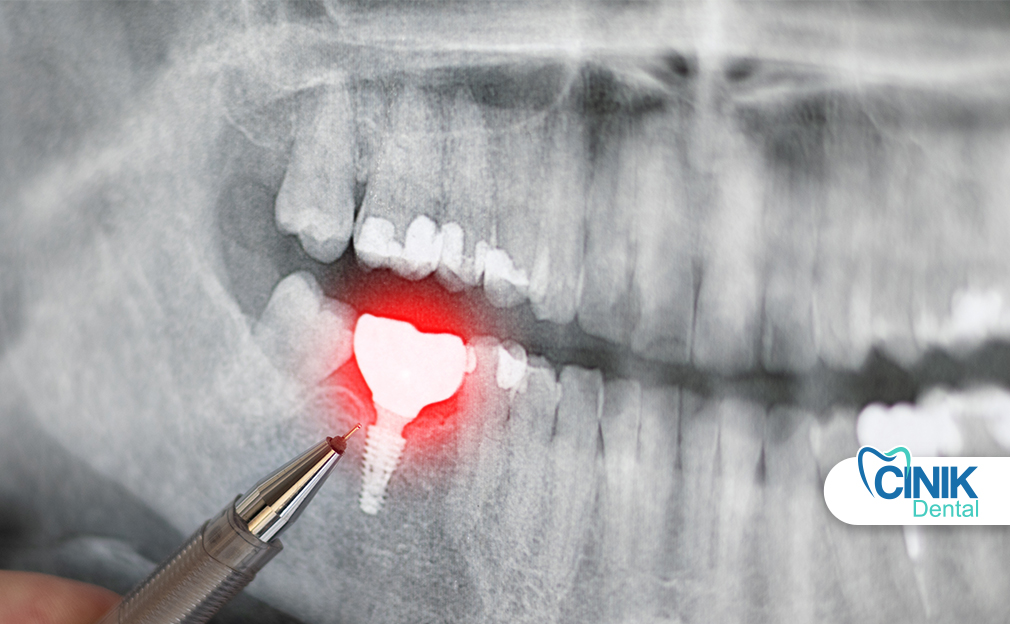

How Do Dental Implants Replace Missing Teeth?

Quick Answer: Implants use a metal root and a new tooth to fill a gap forever.

Dental implants replace both the tooth root and crown. Dentists place a titanium post into the jawbone. The bone bonds with the implant through a process called osseointegration (Brånemark et al., 1977).

Implants prevent bone loss after tooth loss. They also keep nearby teeth from shifting. Research shows that dental implants offer high long-term success rates and improve quality of life (Albrektsson et al., 2011).

Implants feel stable and natural. Patients brush and floss them like real teeth. They remain the gold standard for replacing missing teeth in modern dentistry.